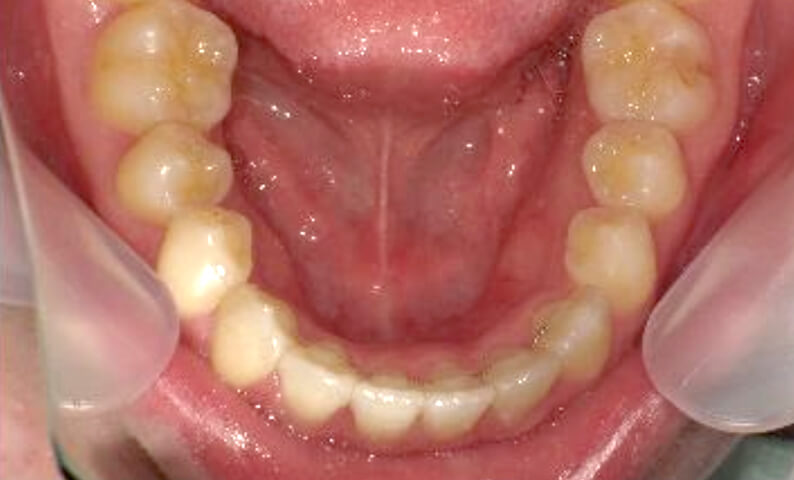

症例_003 下顎だけの部分矯正

治療期間:8ヶ月金額:30万円+税男性前歯のガタガタ下の前歯だけ